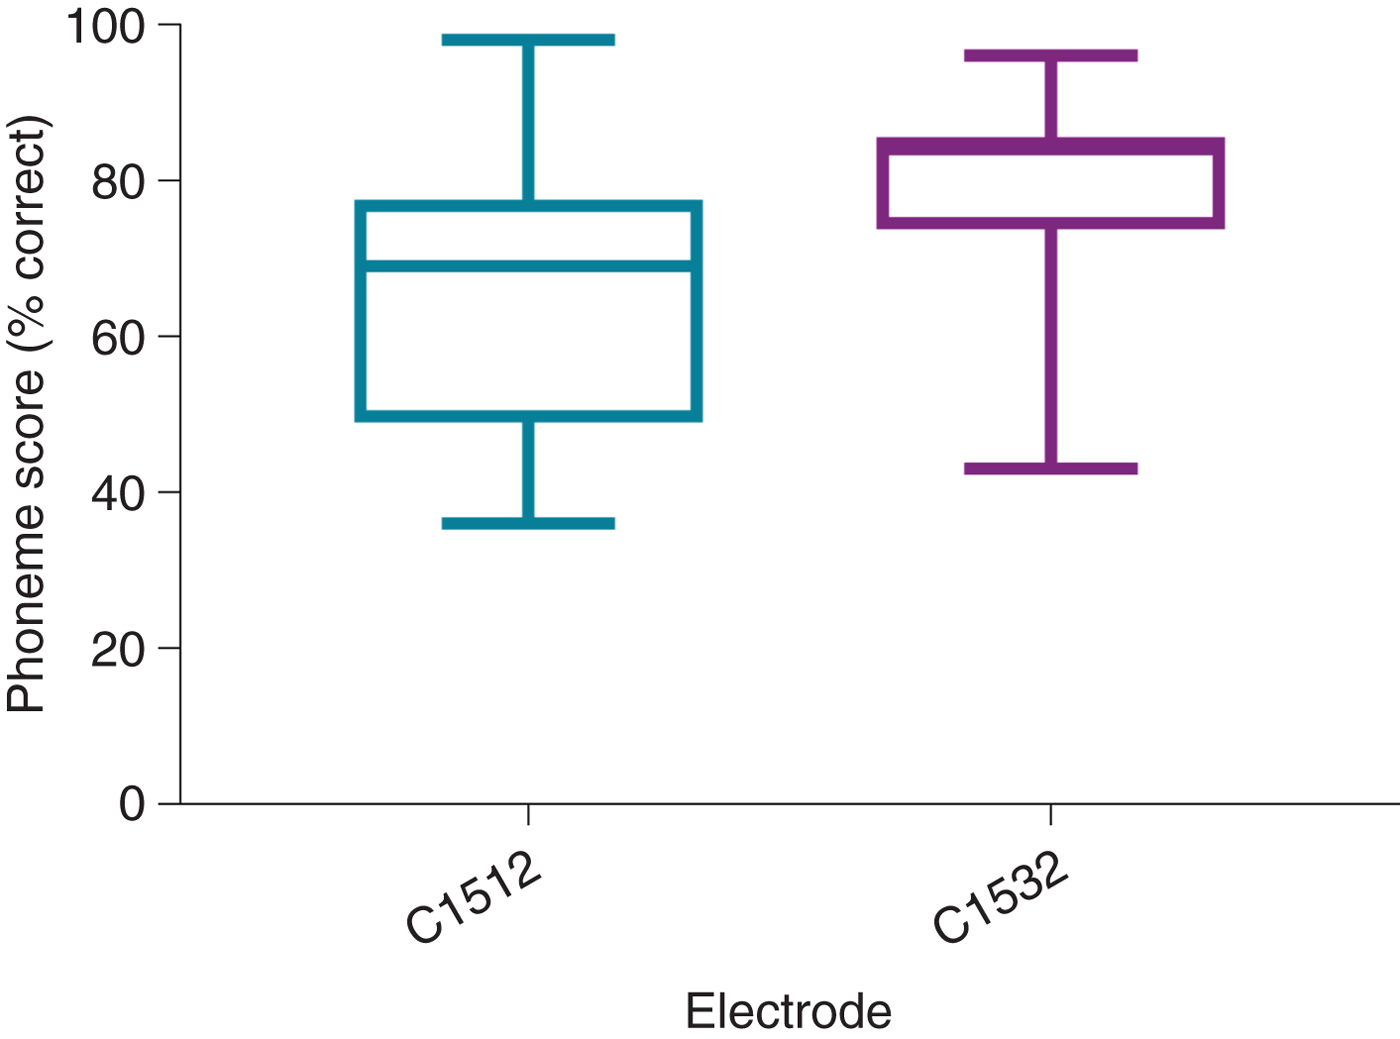

CI512 versus CI532

All patients with CI532 electrodes had post-lingual onset hearing loss. The CI532 electrode outcomes were therefore only compared to post-lingual CI512 electrode patients. Phoneme scores at 3 and 12 months post-implantation were higher in the CI532 electrode group (65 per cent) compared to the CI512 electrode group (79 per cent) (Table 5). Furthermore, when compared to the CI512 electrode patients with complete scala tympani insertion, the CI532 electrode group demonstrated better performance. However, phoneme scores were higher pre-operatively for the CI532 electrode group than for the CI512 electrode group (Table 5). Therefore, in order to match the CI512 and CI532 electrode groups, the patients in the CI512 electrode group with lower quartile pre-operative phoneme scores were removed. After matching the groups, the differences become smaller, but remained significant 12 months post-implantation (69 per cent vs 80 per cent) (Table 6 and Figure 7).

Fig. 7. Twelve-month post-implantation phonemes scores of post-lingual patients with CI512 or CI532 electrodes. All electrodes were in scala tympani. The groups were matched by removing the patients with CI512 electrodes who had lower quartile pre-operative phoneme scores.

In this study, all CI532 electrodes were located in scala tympani, as reported by Aschendorff et al. in the initial clinical trial.Reference Aschendorff, Briggs, Brademann, Helbig, Hornung and Lenarz13 McJunkin et al. reported that only 74 per cent (17 out of 23) of CI532 electrode recipients had full scala tympani insertion, however.Reference McJunkin, Durakovic, Herzog and Buchman12 This study is the first to report 12-month post-operative consonant–vowel–consonant word results for CI532 electrode recipients. These recipients achieved significantly better consonant–vowel–consonant word results compared to CI512 electrode recipients. This difference was not only demonstrated in a comparison with the overall group of CI512 electrode recipients intended to have scala tympani insertion but also when compared to the group with confirmed scala tympani localisation. Furthermore, in order to better match the CI512 and CI532 electrode groups, those patients with CI512 electrodes who had lower quartile pre-operative consonant–vowel–consonant word scores were removed from the comparison, and the speech performance of the CI532 electrode group remained better. This study included a low number of CI532 electrode recipients, however, and so it is difficult to draw any definite conclusions regarding comparative outcomes.